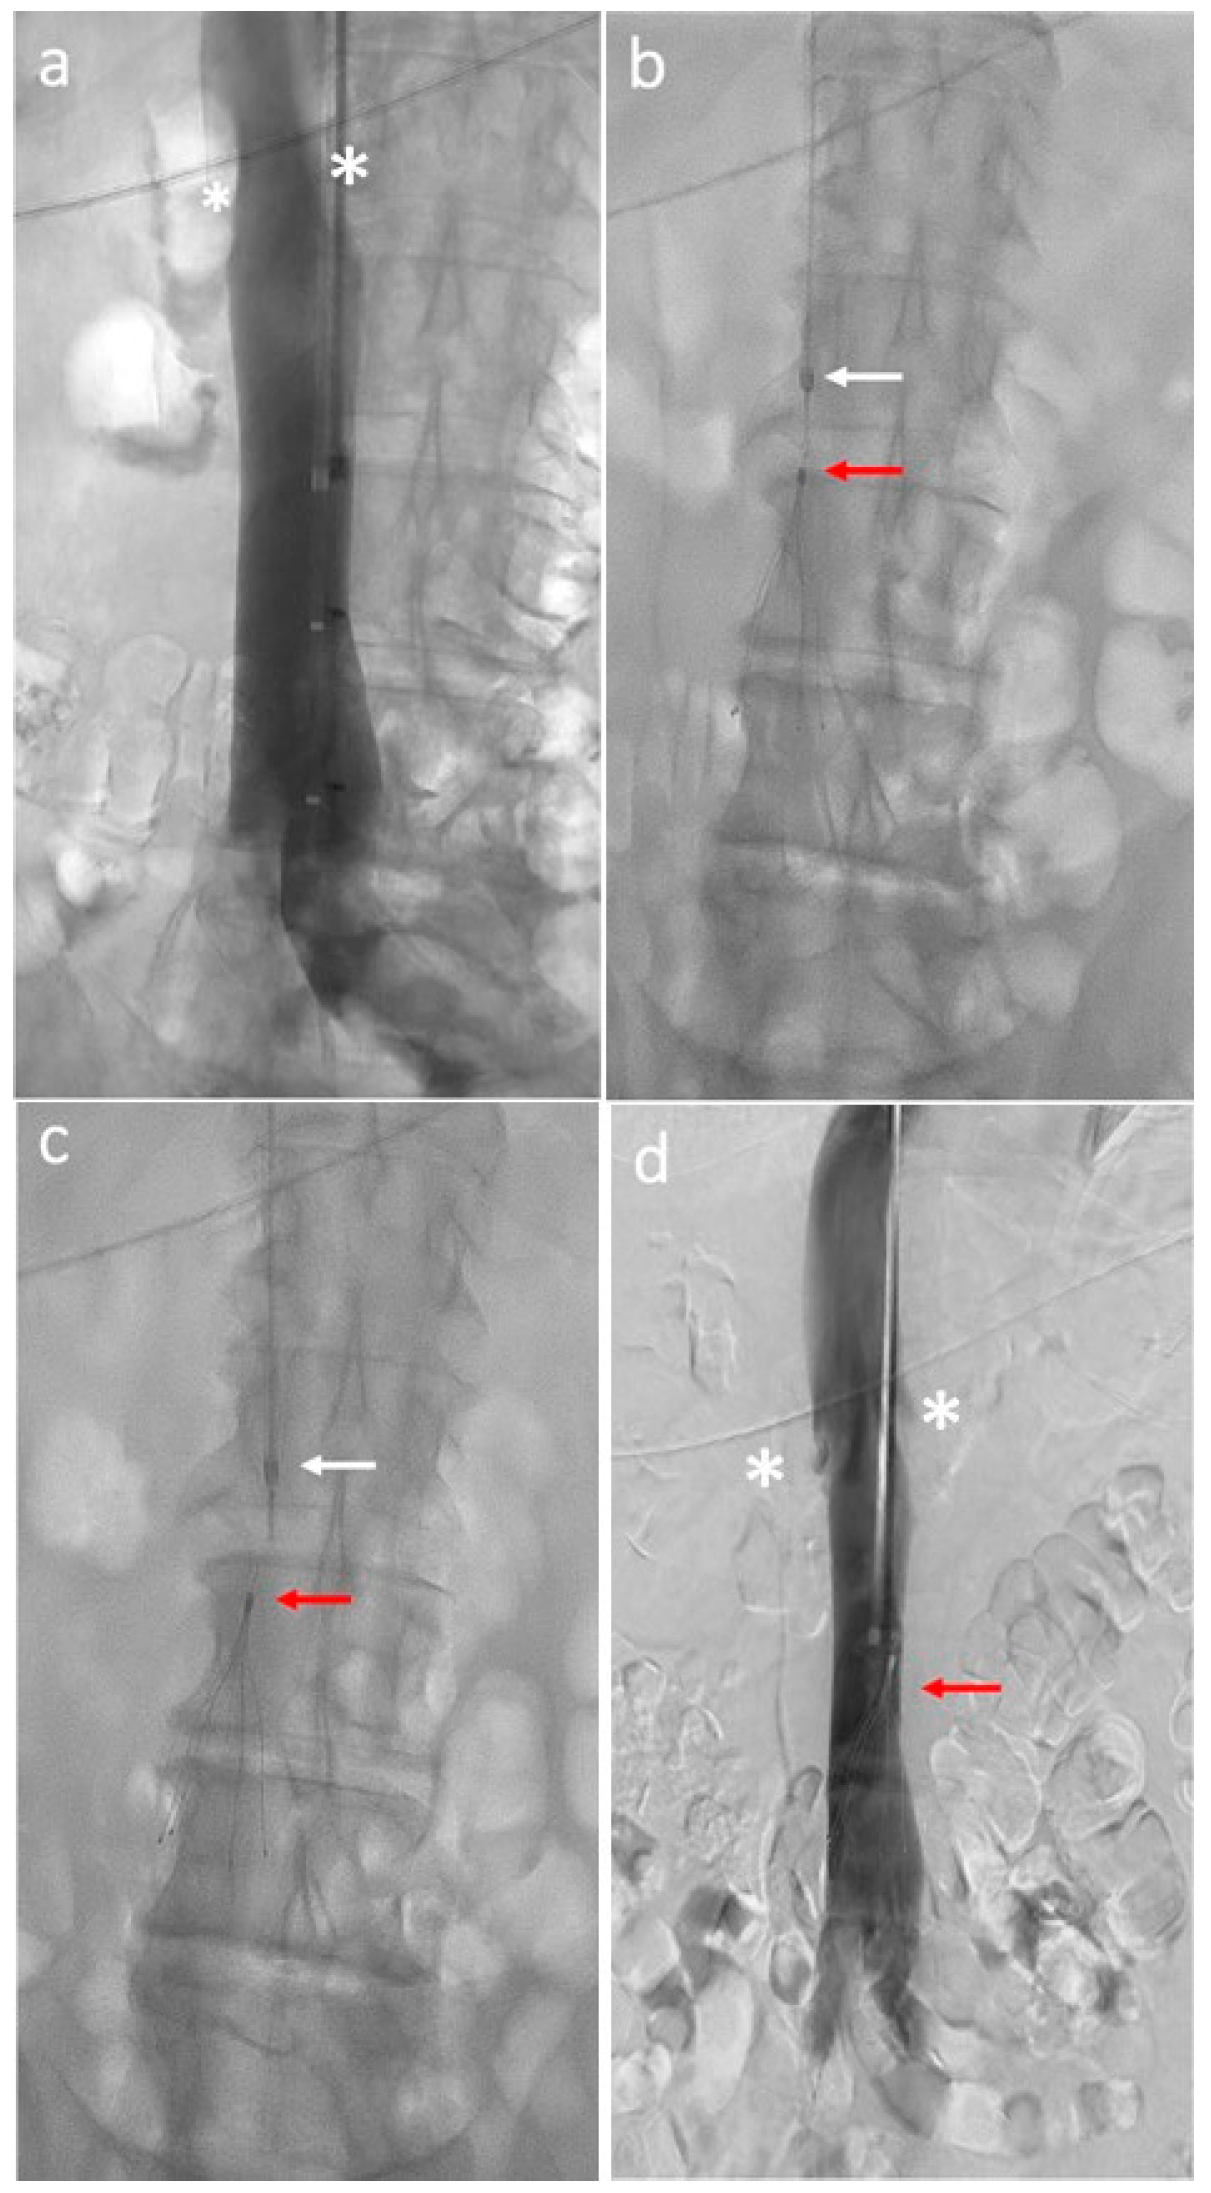

4. Inferior Vena Cava Placement Procedure

5.2. Caval Wall Penetration